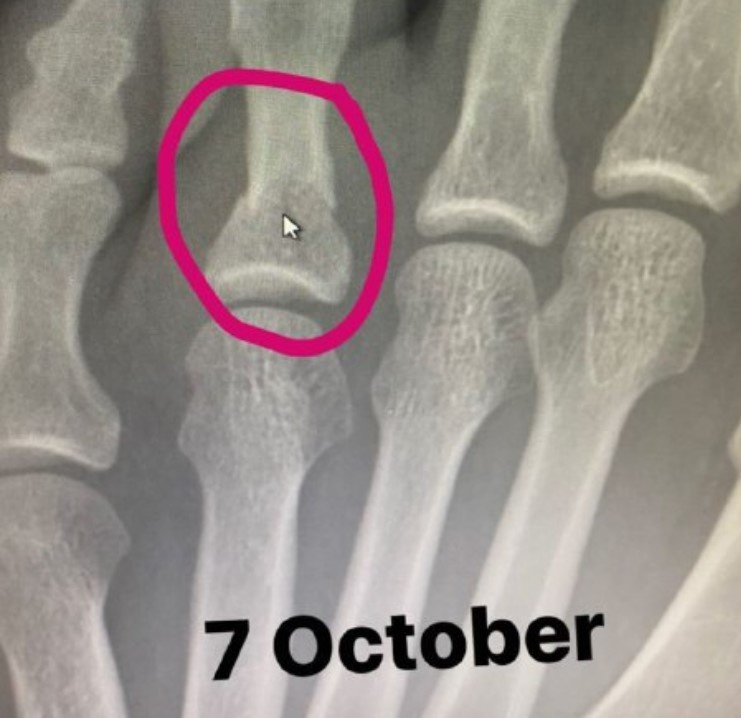

Президент UFC Дэйна Уайт сообщил, что чемпион промоушена в легком весе Хабиб Нурмагомедов получил травму перед боем с Джастином Гэтжи на UFC 254. Боец сломал ногу за три недели до поединка. У него сломаны два пальца на ноге и сломана кость на ступне.

Доказательством перелома послужил рентгеновский снимок, который Нурмагомедов выложил на своей странице в Инстаграм.

На первом фото представлен здоровый палец борца до травмы, а на втором — отекшая нога уже после происшествия.